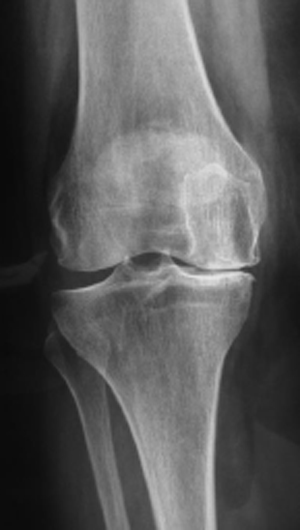

La razón primordial que indica colocar una prótesis de rodilla es el desgaste articular que origina dolor e incapacidad debido a la destrucción importante que presenta la articulación y que pueden ser originadas por Osteoartritis avanzada y Artritis Reumatoide.

En la radiografía de la izquierda se observa la asimetría entre los espacios de la articulación de la rodilla, el lado lateral se observa separado y hacia el lado contrario se presenta un desgaste o pinzamiento entre los dos huesos que se traduce como una pérdida del cartílago o cojinete articular.

• Cuando su médico detecta radiográficamente un desgaste y/o destrucción

importante de la articulación (Osteoartritis avanzada).